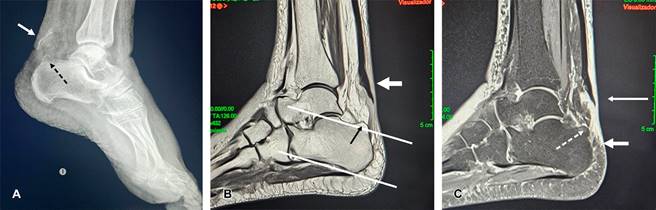

Figura 1: A) Radiografía lateral de tobillo izquierdo que muestra: avulsión del tendón de Aquiles con lámina ósea de la entesis (flecha blanca) en calcáneo con deformidad de Haglund (flecha negra). B) Resonancia magnética (RM) ponderada en T1, se observa avulsión del tendón de Aquiles, desplazado 4 cm (flecha blanca) y trazo de líneas paralelas para corroborar deformidad de Haglund (flecha negra). C) RM en secuencia STIR mostrando las lesiones descritas (flechas), con gran edema de la grasa de Kager.

El tendón de Aquiles transmite la fuerza de la contracción del tríceps sural (TS) al calcáneo, la contracción y/o estiramiento brusco del TS en pacientes mayores puede generar avulsión del tubérculo posterior del calcáneo debido a mala calidad ósea o avulsión de la entesis del tendón de Aquiles (como el caso que se presenta), afectándolo por tendinosis crónica debido a presencia de deformidad de Haglund (Figura 1). Las fracturas por avulsión del tendón de Aquiles representan de 1.3 a 2.7% de todas las fracturas del calcáneo.1-3 En este caso se trata de una fractura avulsión de la entesis del tendón de Aquiles con un fragmento óseo mínimo correspondiendo al tipo I de la clasificación de Beavis; los factores de riesgo son: edad, tendinopatía crónica, diabetes mellitus, nefropatía, uso de fármacos como esteroides o quinolonas.